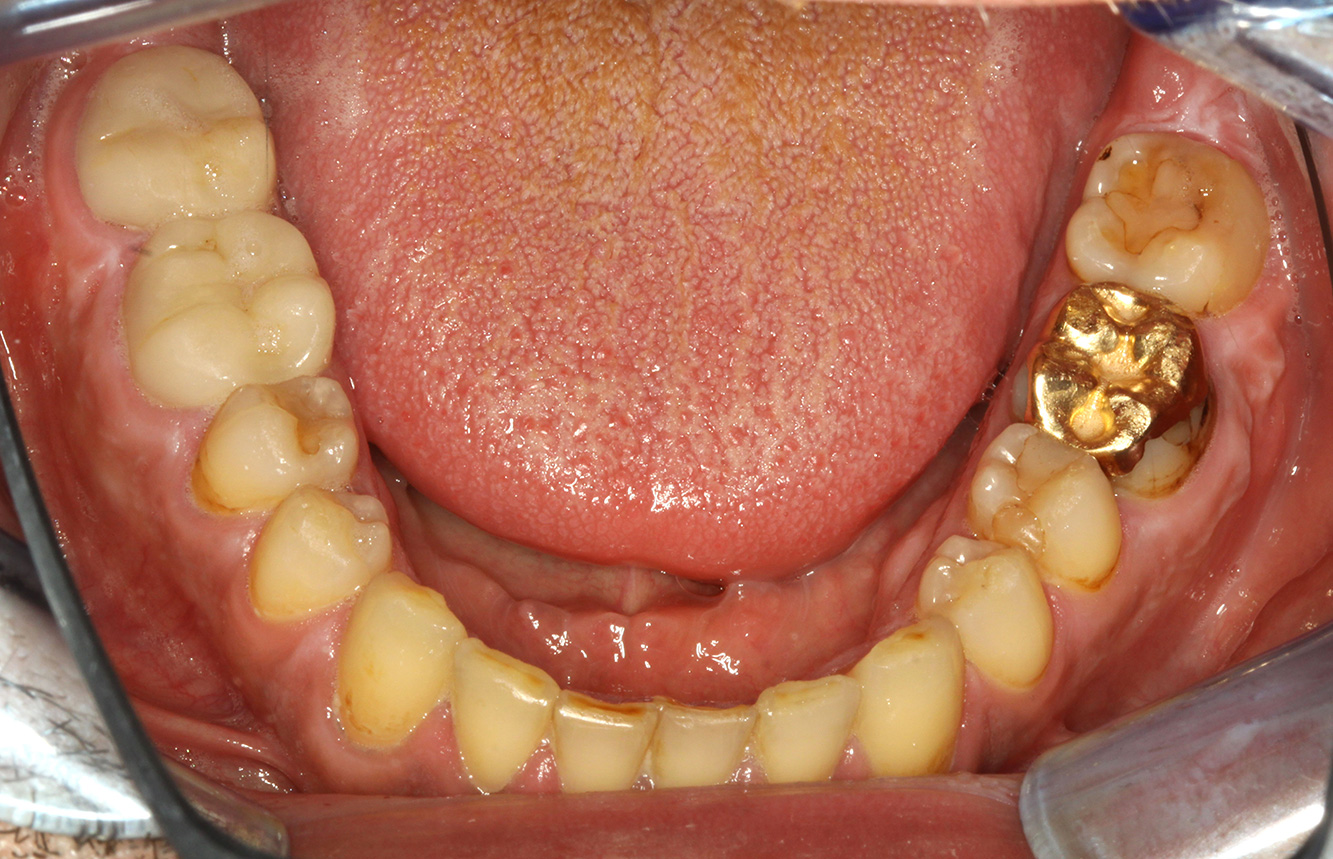

Der gesunde Patient mit parodontaler Vorerkrankung & Periimplantitis

Ein 52-jähriger Patient stellt sich zur Präventionssitzung vor. Der Patient hat keine Allgemeinerkrankungen und nimmt keine Medikamente ein. Er hat verschiedene zahnärztliche Versorgungen und zudem zwei aktive kariöse Läsionen. Außerdem verfügt der Patient über vier Implantate (2., 3. und 4. Quadrant). Es zeigt sich eine parodontale Vorerkrankung (Stadium IV, Grad B). Derzeit herrschen stabile parodontale Verhältnisse, lediglich am Implantat regio 36 zeigen sich Sondierungstiefen (ST) von 5 mm. Zudem lässt sich eine Gingivitis feststellen. mehr Infos